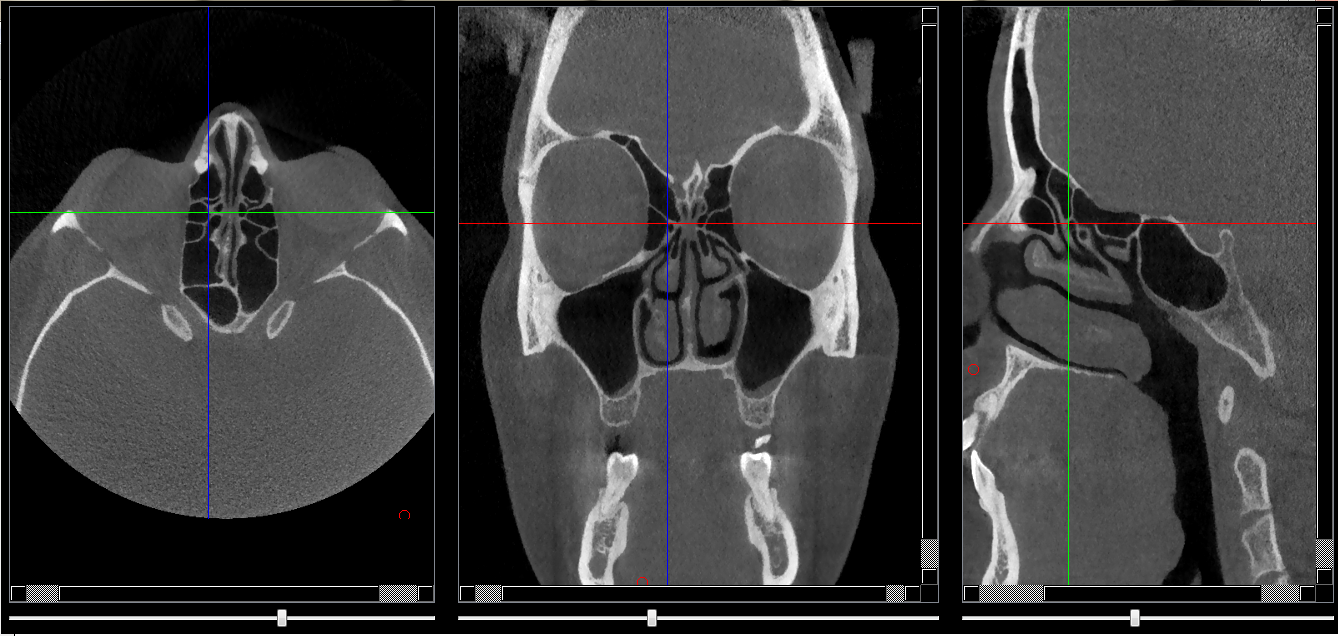

Structures osseuses

Repères anatomiques

- Coupe transversale

- Début : Cornet nasal moy

- Fin : Fissure orbitaire sup

- Coupe frontale

- Début : Os nasale

- Fin : Sinus sphénoide

- Coupe saggitale

- Début : Paroi interne de l'orbite

- Fin : Crista galli

Infos sur l'image

- Auteur : Pr Bourzgui

- Co-auteur : Dr Makoure

- Affiliation : Orthopédie dento-faciale

- Date production : 2019